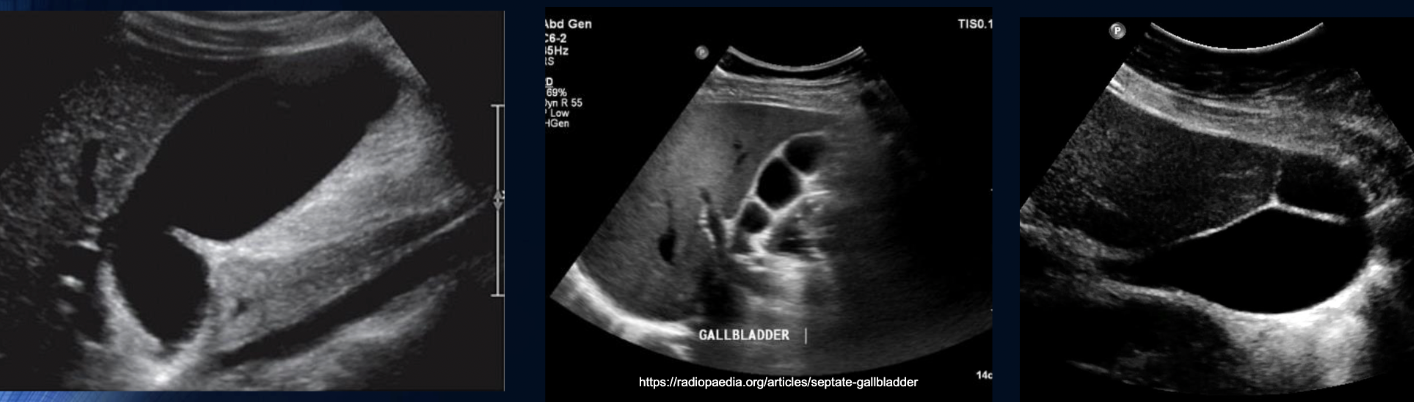

are these pathology or congenital?

Congenital